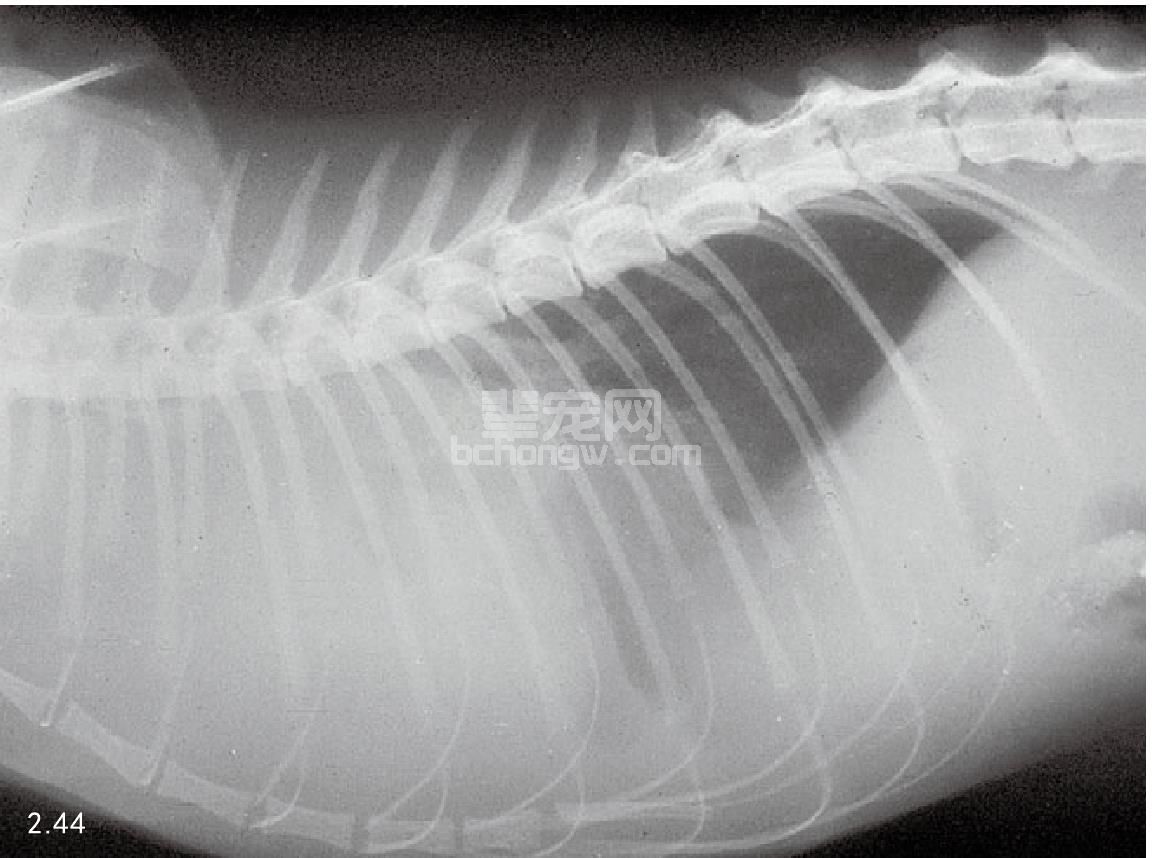

图2.44 患有前部胸腔纵隔淋巴瘤的家养长毛猫的侧面X线片。